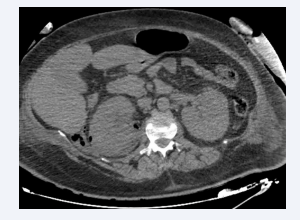

Axial section of an abdominal CT scan after intravenous  contrast injection at portal time showing an enlarged left kidney  with a nephrographic defect and surrounded by a posterior perirenal  collection containing air bubbles. The appearance is compatible with  class 3A EPN according to Huang et al.

Figure 1: Axial section of an abdominal CT scan after intravenous contrast injection at portal time showing an enlarged left kidney with a nephrographic defect and surrounded by a posterior perirenal collection containing air bubbles. The appearance is compatible with class 3A EPN according to Huang et al.